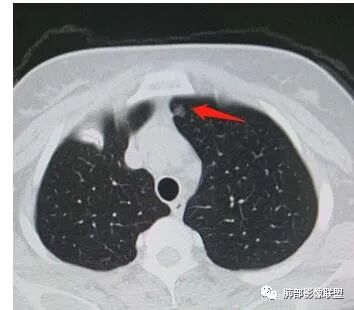

一、先讨论GGN吧

1、密度?MGGN?PGGN?

2、边界?清?不清?

3、有无收缩力?有胸膜牵拉?毛刺?

南边

4、血管连通 移动:3型?4型?

两条都进入,相互交通-4

常规判断还需要大小、CT值

大家诊断啥?

为啥不是原位?

有收缩,牵拉

血管进入增粗,胸膜牵拉

有月牙 两条都进入,相互交通-4 胸膜牵拉

不是纯的GGO

血管进入

二.左肺上叶前段磨玻璃结节:

该结节较大,边界清楚,小叶间隔阻挡特征相当明显,微浸润腺癌的诊断几乎没有争议!